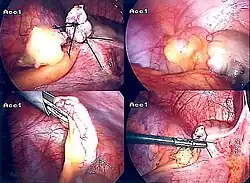

The surgical procedure for the removal of the appendix is called an appendectomy. A negative appendectomy constitutes the removal of a normal appendix with no sign of inflammation in histopathology examination. The prevalence of negative appendectomy varies but has been estimated to 13%.[76] Appendectomy can be performed through open or laparoscopic surgery. Laparoscopic appendectomy has several advantages over open appendectomy as an intervention for acute appendicitis.[91]

Laparoscopic appendectomy

Laparoscopic appendectomy was introduced in 1983 and has become an increasingly prevalent intervention for acute appendicitis.[95] This surgical procedure consists of making three to four incisions in the abdomen, each 0.25 to 0.5 inches (6.4 to 12.7 mm) long. This type of appendectomy is made by inserting a special surgical tool called a laparoscope into one of the incisions. The laparoscope is connected to a monitor outside the person's body, and it is designed to help the surgeon inspect the infected area in the abdomen. The other two incisions are made for the specific removal of the appendix by using surgical instruments. Laparoscopic surgery requires general anesthesia, and it can last up to two hours. Laparoscopic appendectomy has several advantages over open appendectomy, including a shorter post-operative recovery, less post-operative pain, and a lower superficial surgical site infection rate. However, the occurrence of an intra-abdominal abscess is almost three times more prevalent in laparoscopic appendectomy than open appendectomy.[96]